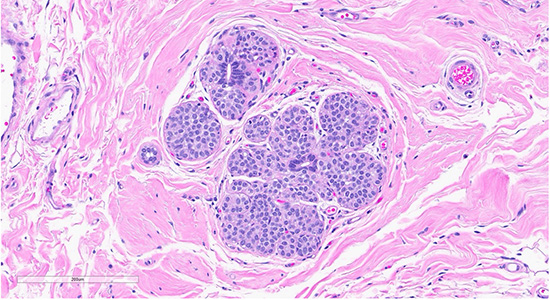

Figure 2: Scattered foci nearby the collagenous spherulosis exhibited mildly enlarged lobules filled with bland monomorphic cells (ALH/LCIS (top)., cellular dyshesion is better appreciated at high power (bottom).

Histological examination revealed lobules containing cells arranged in a cribriform pattern with eosinophilic to basophilic, round to oval, collagen-rich spherules (in this case mucinous spherules - may be called mucinous spherperolosis instead). Adjacent regions demonstrated a monomorphic proliferation of mildly atypical cells with round nuclei, indistinct nucleoli, and dyshesive features, along with intracytoplasmic lumina. Other foci were composed of ducts with monomorphic cells displaying ovoid to rounded nuclei in a solid and cribriform pattern, each focus measuring less than 2 mm. A focal area displayed ducts filled with polymorphous cells with peripheral elongated clefts. Additional ducts exhibited an architecturally “flat” pattern without cytologic atypia. The epithelial lining cells were predominantly columnar, with elongated nuclei oriented perpendicular to the basement membrane.